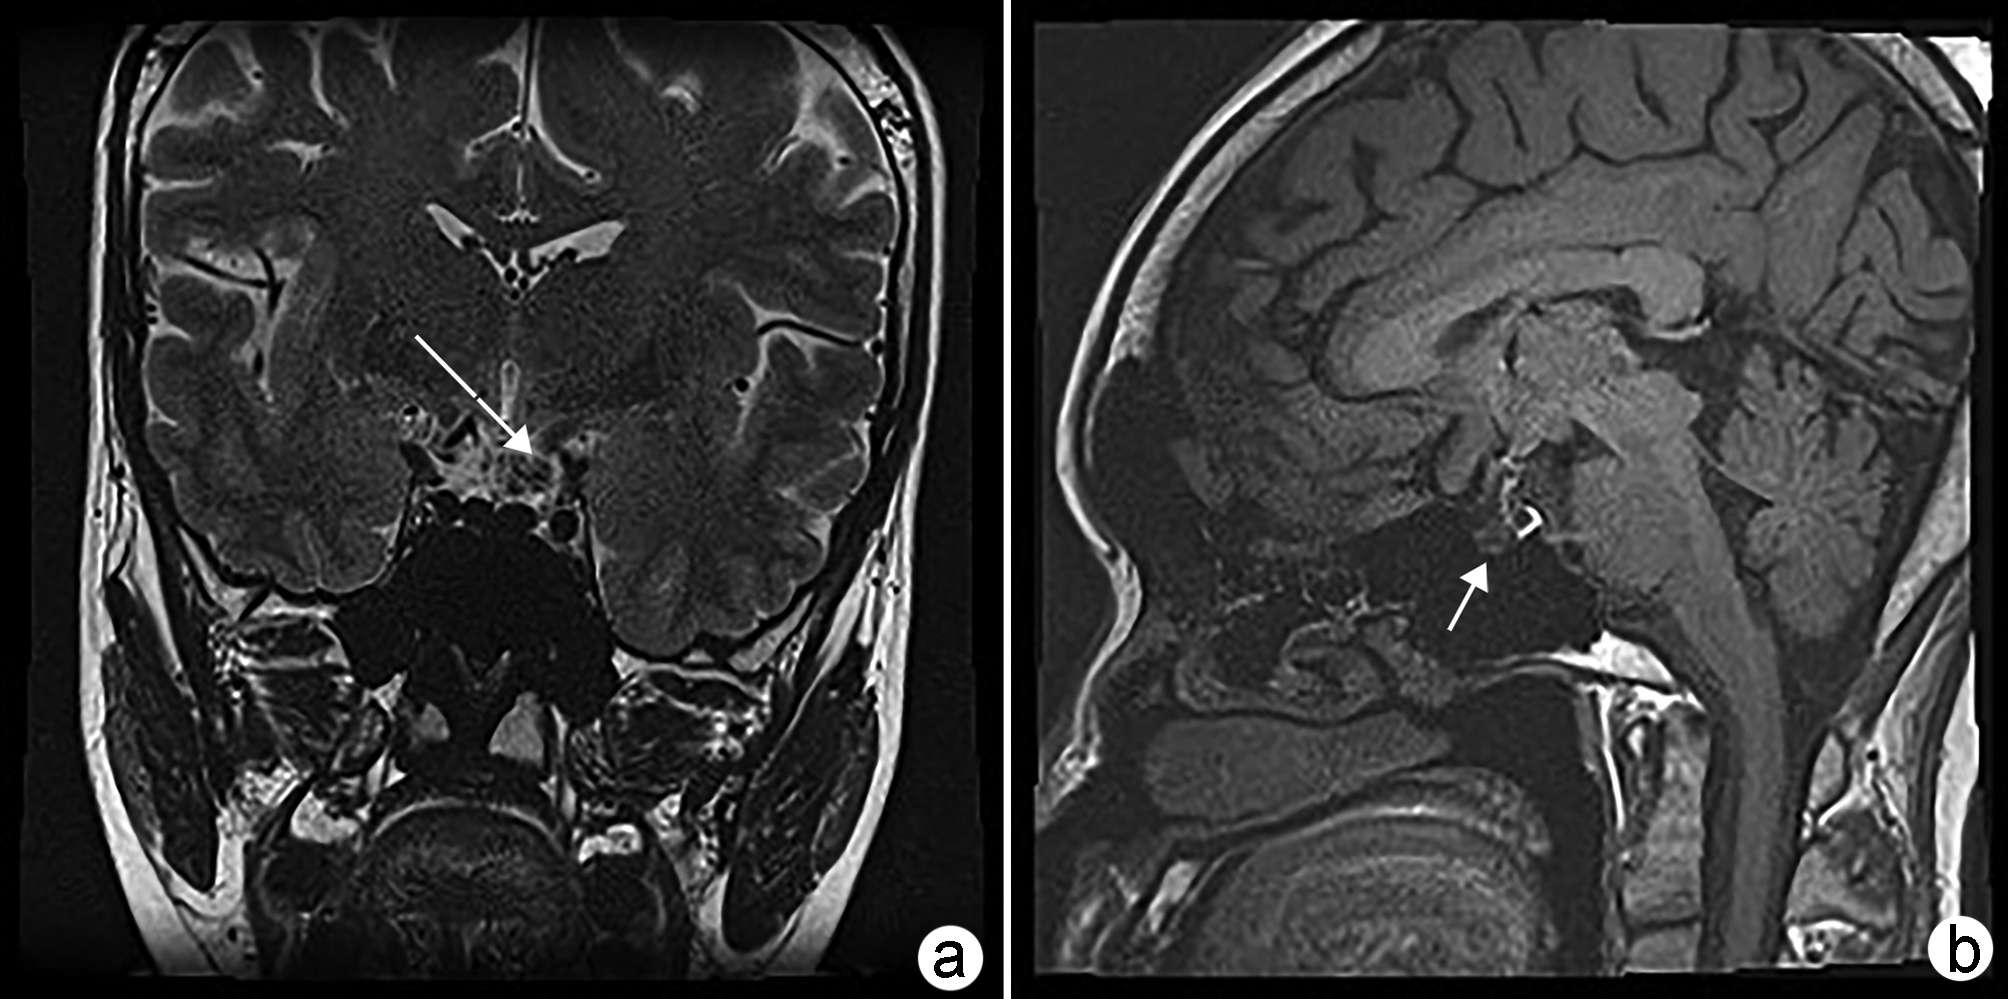

Risk factors for cognitive impairment associated with nonalcoholic fatty liver disease

Cheng ZHOU, Ran JIA, Jingjing WEI, Chenlu ZHAO, Dongfang SHANG, Wenxia ZHAO

2022, 38(11): 2592-2595. DOI: 10.3969/j.issn.1001-5256.2022.11.031

Abstract(858) HTML (303) PDF (1863KB)(75)

Abstract:

At present, non-alcoholic fatty liver disease (NAFLD) has become one of the most common chronic liver diseases in the world. Recent studies have shown that varying degrees of central nervous system dysfunction can occur during the progression of NAFLD, including cognitive impairment and emotional imbalance. This article summarizes the main risk factors for NAFLD-related cognitive impairment at different stages, so as to provide a basis and ideas for the early prevention and clinical treatment of this disease.